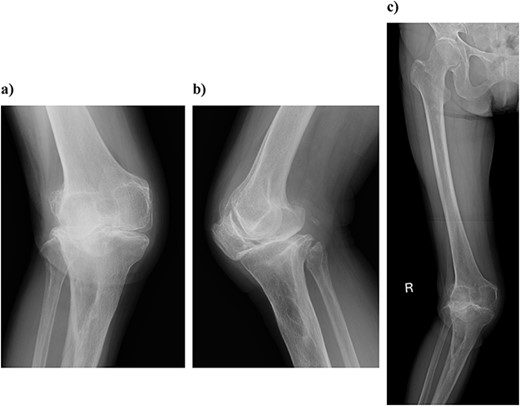

On physical examination, the patient extension and flexion were − 20° and 130°. A defect of the tibial tubercle was observed. The Knee Society (KS) score was 44 points, and the Knee Society function (KS-F) score was 70 points. A plain radiography showed valgus knee osteoarthritis assessed as Kellgren–Lawrence grade 4. In addition, a well-defined translucent image of bone appeared near the central part of the proximal tibia and no tibial tubercle could be observed (Fig. 1). Magnetic resonance imaging (MRI) of the right knee joint showed the patellar tendon appeared from the attachment on the patella with continuity to the tibial bone marrow in T1- and T2-weighted imaging (Fig. 2).

Plain radiography at the patient’s first visit: (a) standing front, (b) lateral side and (c) thigh, standing, front, full length. Valgus knee osteoarthritis and well-defined osteoporosis near the central part of the proximal tibia can be seen, and the rough surface of the tibia has been worn away.